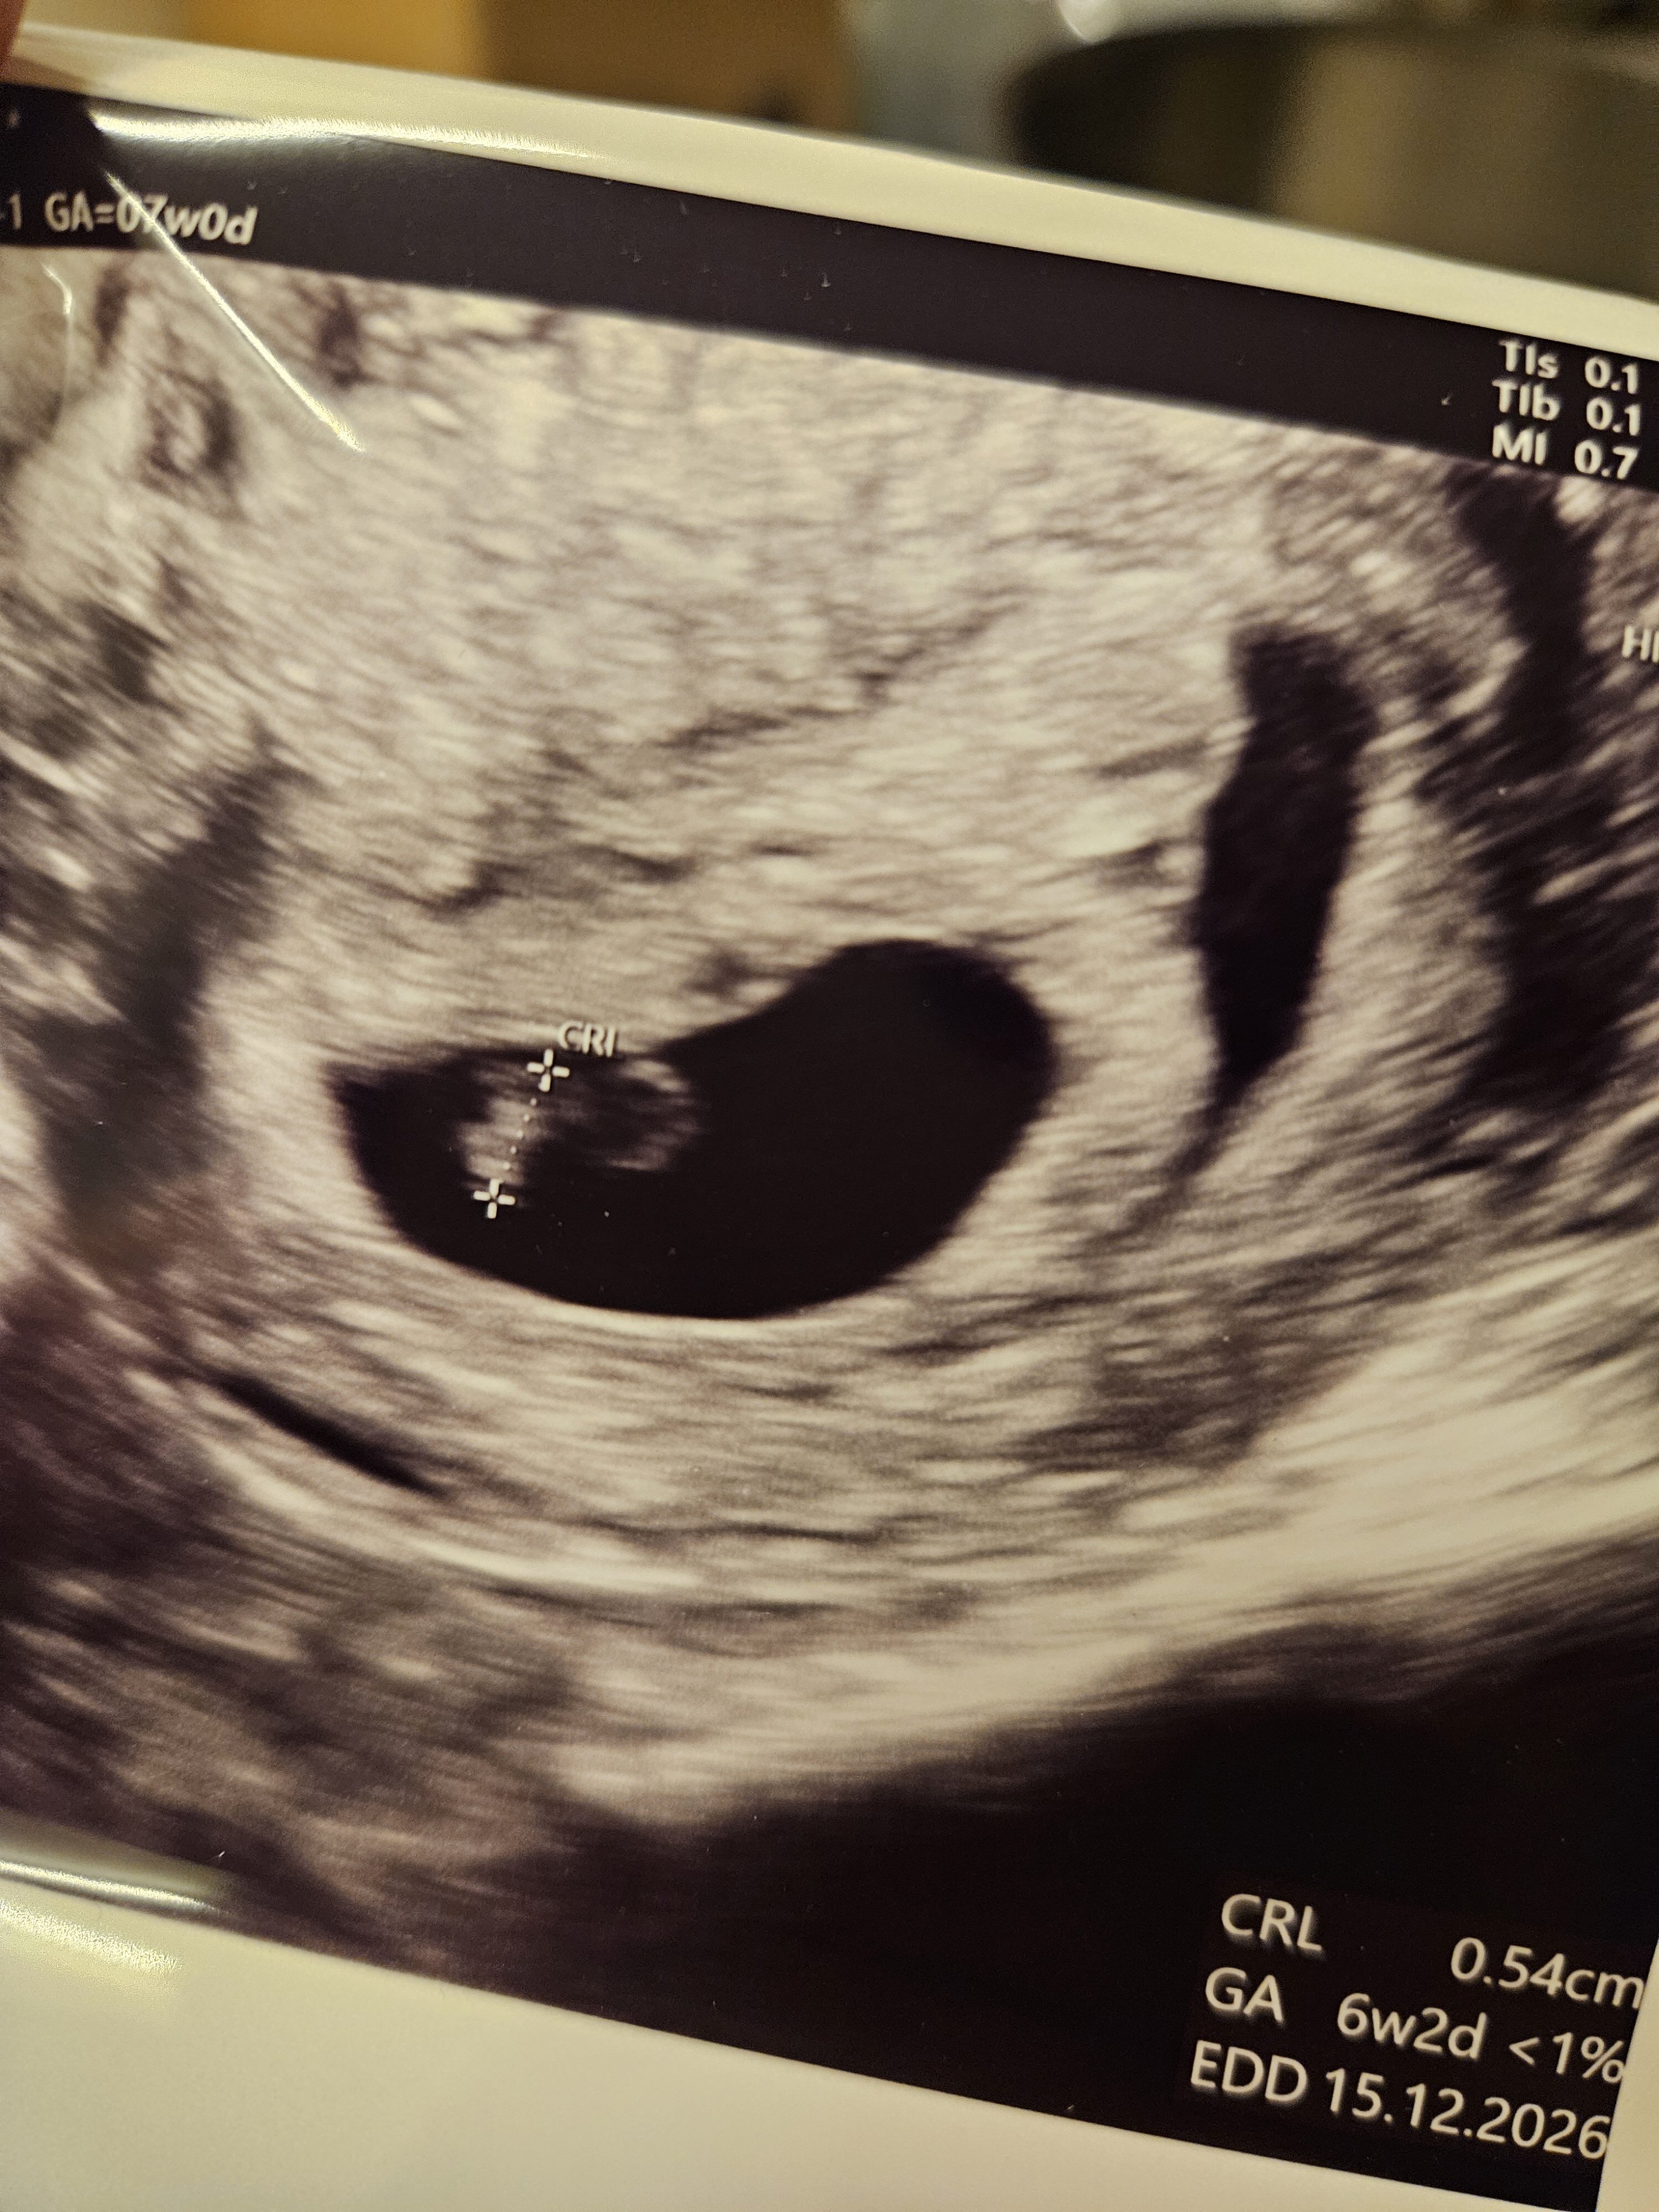

1000023905.jpg

Zdjęcie kropki ;)